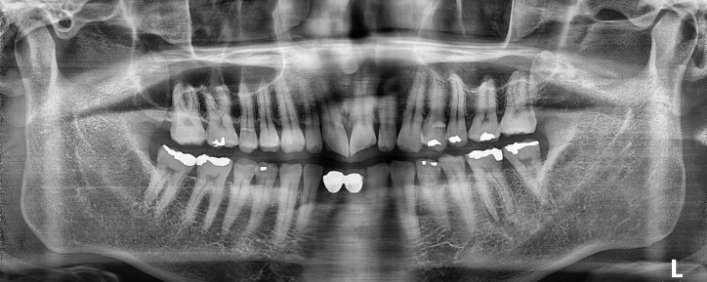

박** 환자분 (오른쪽 상하악 사랑니 동시 발치 케이스)

상악의 경우 단순매복으로 발치 및 동시에 하악 잇몸뼈에

깊게 박혀잇는 고난이도 케이스, 잇몸절개 후 치아 분리하여

발치하였으며

해당환자 치과공포증이 있으셨으나 본원 수면치료 병행하여 편안한

수술 진행되어 만족하심